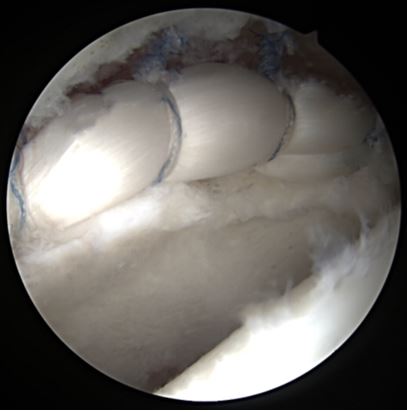

En caso de que el tratamiento conservador resultare subóptimo tras un período considerable, se debe plantear la corrección quirúrgica, esta se realiza, en la mayoría de los casos, de forma artroscópica (el objetivo es la preservación de la articulación efectuando reparación de labrum, femoroplastia y/o acetabuloplastia) (Fig. 7)19. Ante una sintomatología severa que comprometa significativamente la calidad de vida del paciente, puede indicarse tratamiento quirúrgico como primera opción.

Profundizando ligeramente en los puntos clave de la cirugía artroscópica, se prefiere a nivel general la reparación del labrum frente al desbridamiento de la lesión.

Es deseable su reparación anatómica mediante anclajes en su posición natural del borde acetabular, con la intención de restaurar la correcta lubricación, distribución de cargas y estabilidad de la articulación. Se ha visto que la mayoría de las lesiones tienen una longitud de tres horas y que se encuentran en la mayoría de los casos entre las 12 h y las 3 h según un esquema tipo reloj.

En los casos de lesiones graves del labrum en los que la reparación no es viable, se han visto buenos resultados con la reconstrucción (Fig. 9) utilizando aloinjerto para reemplazar el sector lesionado23.